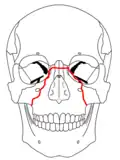

| Le Fort III fractures | |

At the beginning of the 20th century, René Le Fort mapped typical locations for facial fractures; these are now known as Le Fort I, II, and III fractures (right).[7] Le Fort I fractures, also called Guérin or horizontal maxillary fractures,[14] involve the maxilla, separating it from the palate.[15] Le Fort II fractures, also called pyramidal fractures of the maxilla,[16] cross the nasal bones and the orbital rim.[15] Le Fort III fractures, also called craniofacial disjunction and transverse facial fractures,[17] cross the front of the maxilla and involve the lacrimal bone, the lamina papyracea, and the orbital floor, and often involve the ethmoid bone,[15] are the most serious.[18] Le Fort fractures, which account for 10–20% of facial fractures, are often associated with other serious injuries.[15] Le Fort made his classifications based on work with cadaver skulls, and the classification system has been criticized as imprecise and simplistic since most midface fractures involve a combination of Le Fort fractures.[15] Although most facial fractures do not follow the patterns described by Le Fort precisely, the system is still used to categorize injuries.[5]